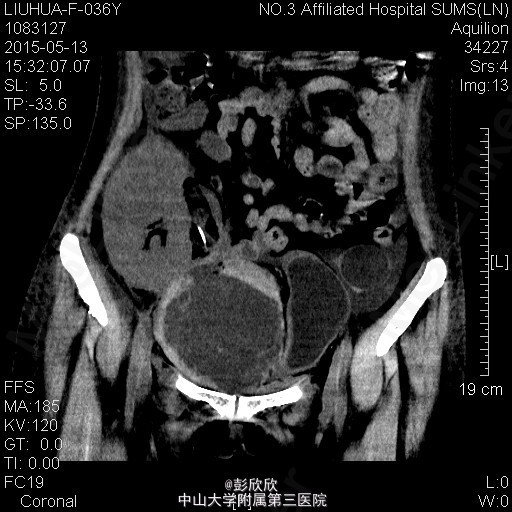

患者女,36岁,因尿毒症与2015-5-9在我院行异体肾移植术,手术过程顺利,术后恢复良好,术后第5天出现移植肾周胀痛不适、头晕、右下肢水肿,检测血常规发现血色素明显降低,考虑体内存在出血,行紧急CT检查提示移植肾下极有一个巨大血肿,考虑有活动性出血,给予输血、使用止血药物等保守治疗措施。

患者右下肢肿胀,移植肾周压痛明显,面色稍苍白。行紧急腹部CT检查提示移植肾下极巨大血肿

诊断:移植肾周巨大血肿,活动性出血? 处理:给予患者紧急输血、补液和药物止血,动态监测血红蛋白,确定没有活动性出血后在彩超引导性行移植肾周穿刺引流术,引出陈旧性积血约600ml。之后密切监测患者生命体征,继续输液、免疫抑制等对症治疗。